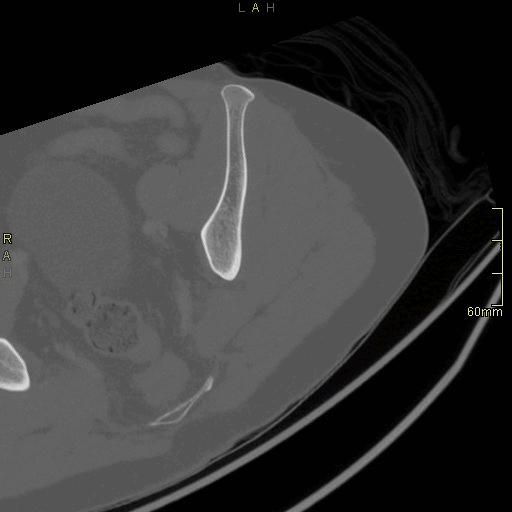

CT Hip Contrast- Bone window (axial)

CT Hip Non Contrast- Bone window (axial)